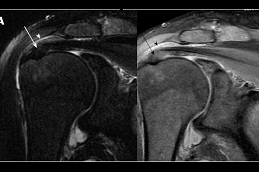

Results:

best prp-injection-for-rotator-cuff-tear in dubai prp injection for rotator cuff tear in dubai prp-injection-for-rotator-cuff-tear in Abu Dhabi

prp-injection-for-rotator-cuff-tear Clinic in Dubai Best prp-injection-for-rotator-cuff-tear Clinic in Dubai Best prp-injection-for-rotator-cuff-tear in Abu Dhabi